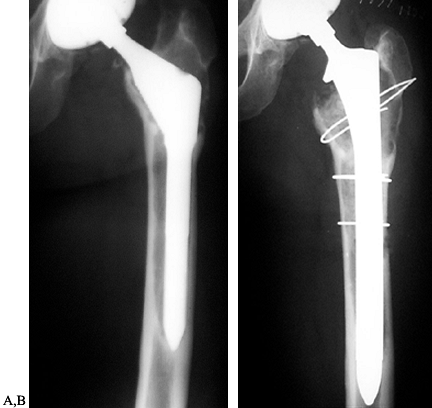

the location of the fracture and the bone quality, and how these

factors affect component stability. Fractures distal to the prosthesis

may not affect fixation and can be treated with conventional open

reduction and internal fixation (ORIF). Fractures that affect component

fixation can sometimes be treated with ORIF or may require revision of

the component. This procedure is covered in Chapter 20 and elsewhere (111).